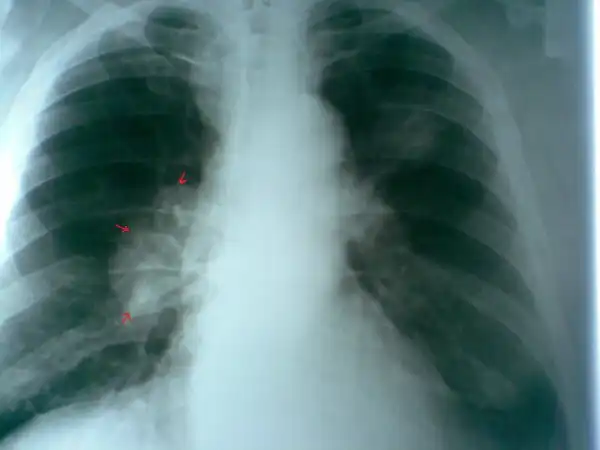

Флюорограмма: